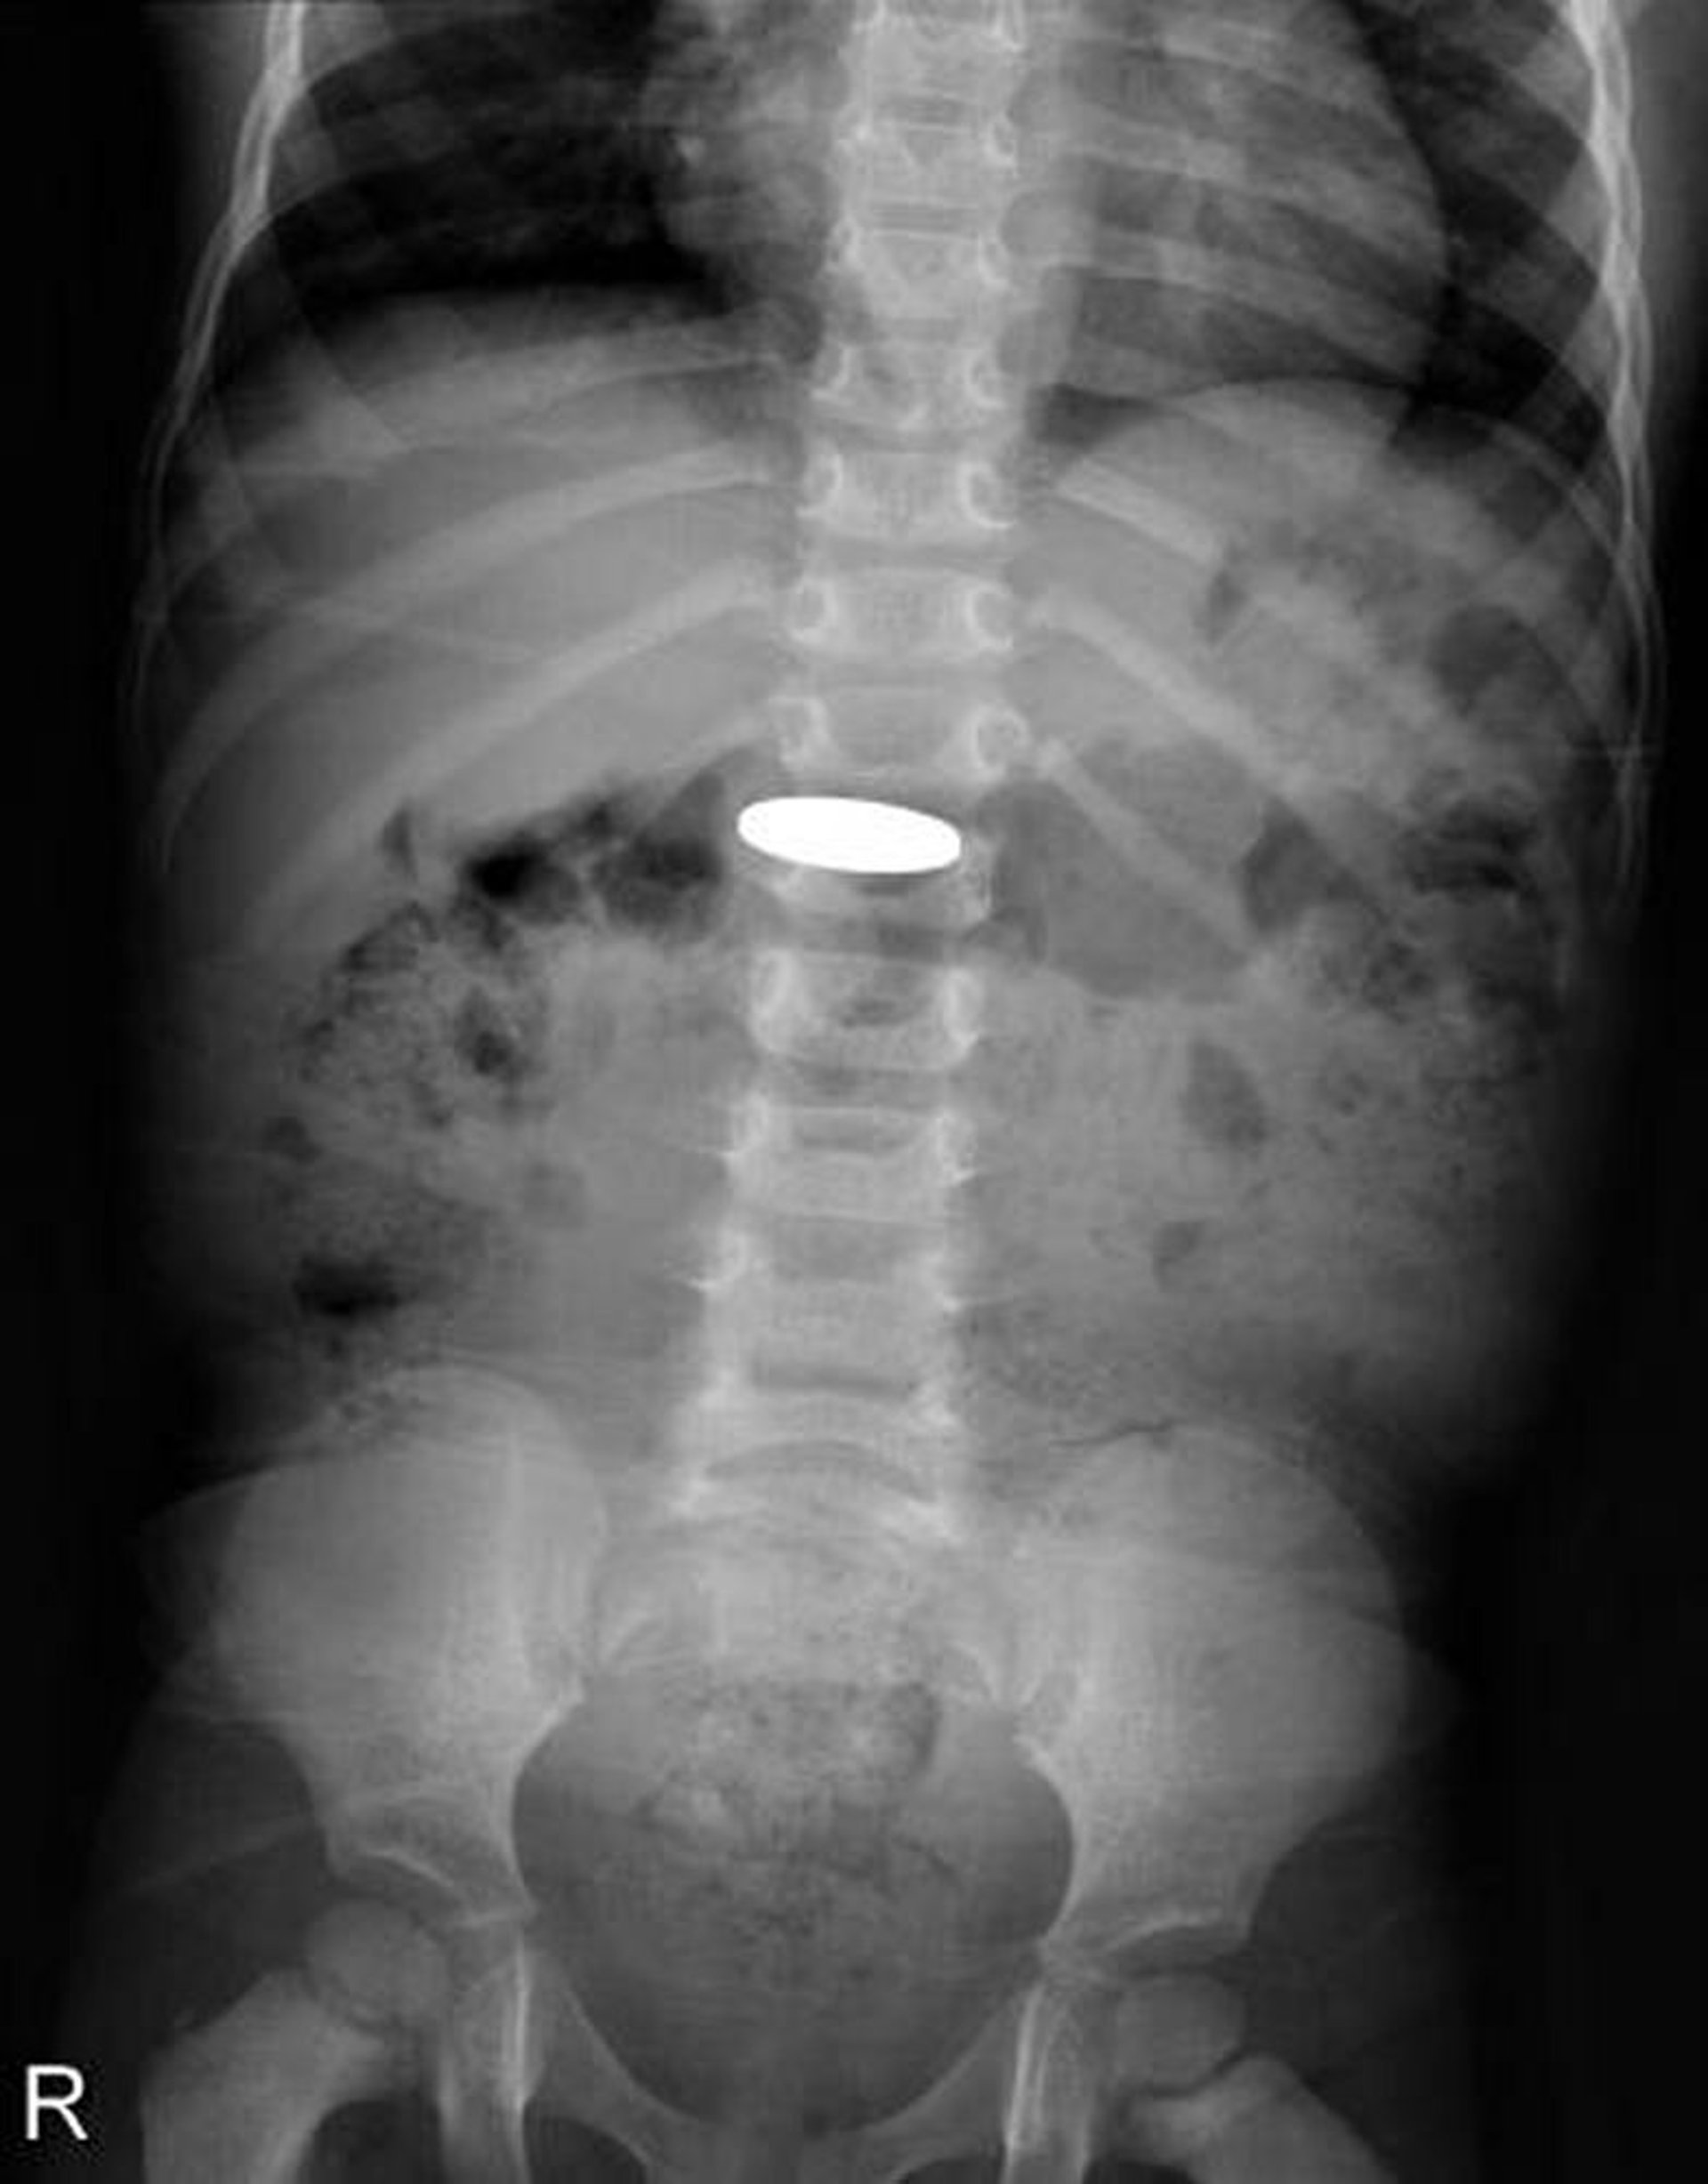

Cuerpo extraño en el tubo digestivo (radiografía)

Esta radiografía muestra una moneda que fue tragada por un niño pequeño.